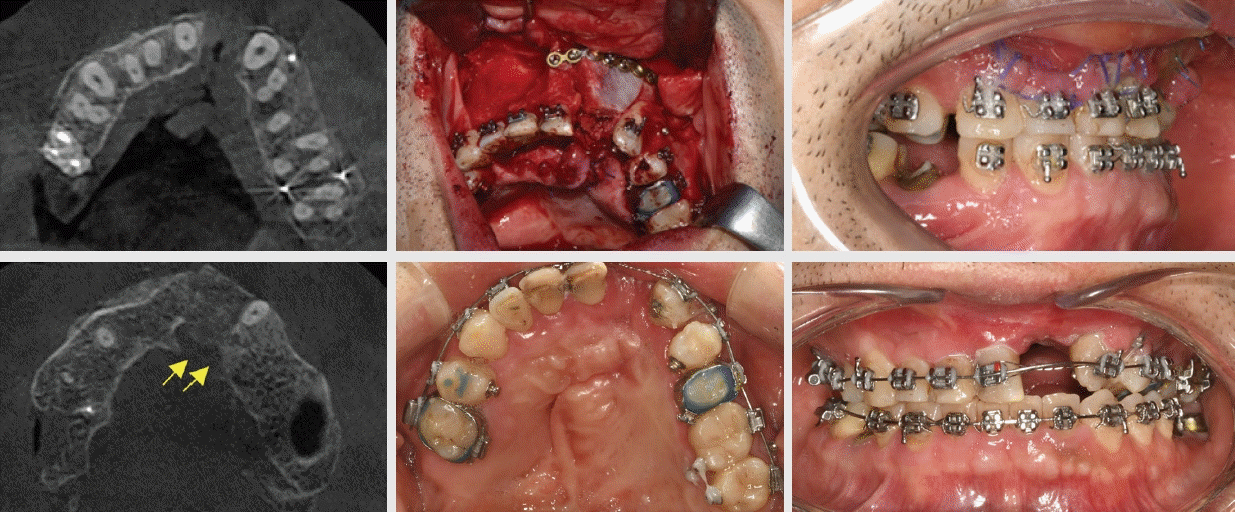

Figure 7.

Upper row: pre-surgical axial view, bone graft, and intra-oral photo

Lower row: 3 month follow-up axial view with new bone bridge, archform, and frontal view.